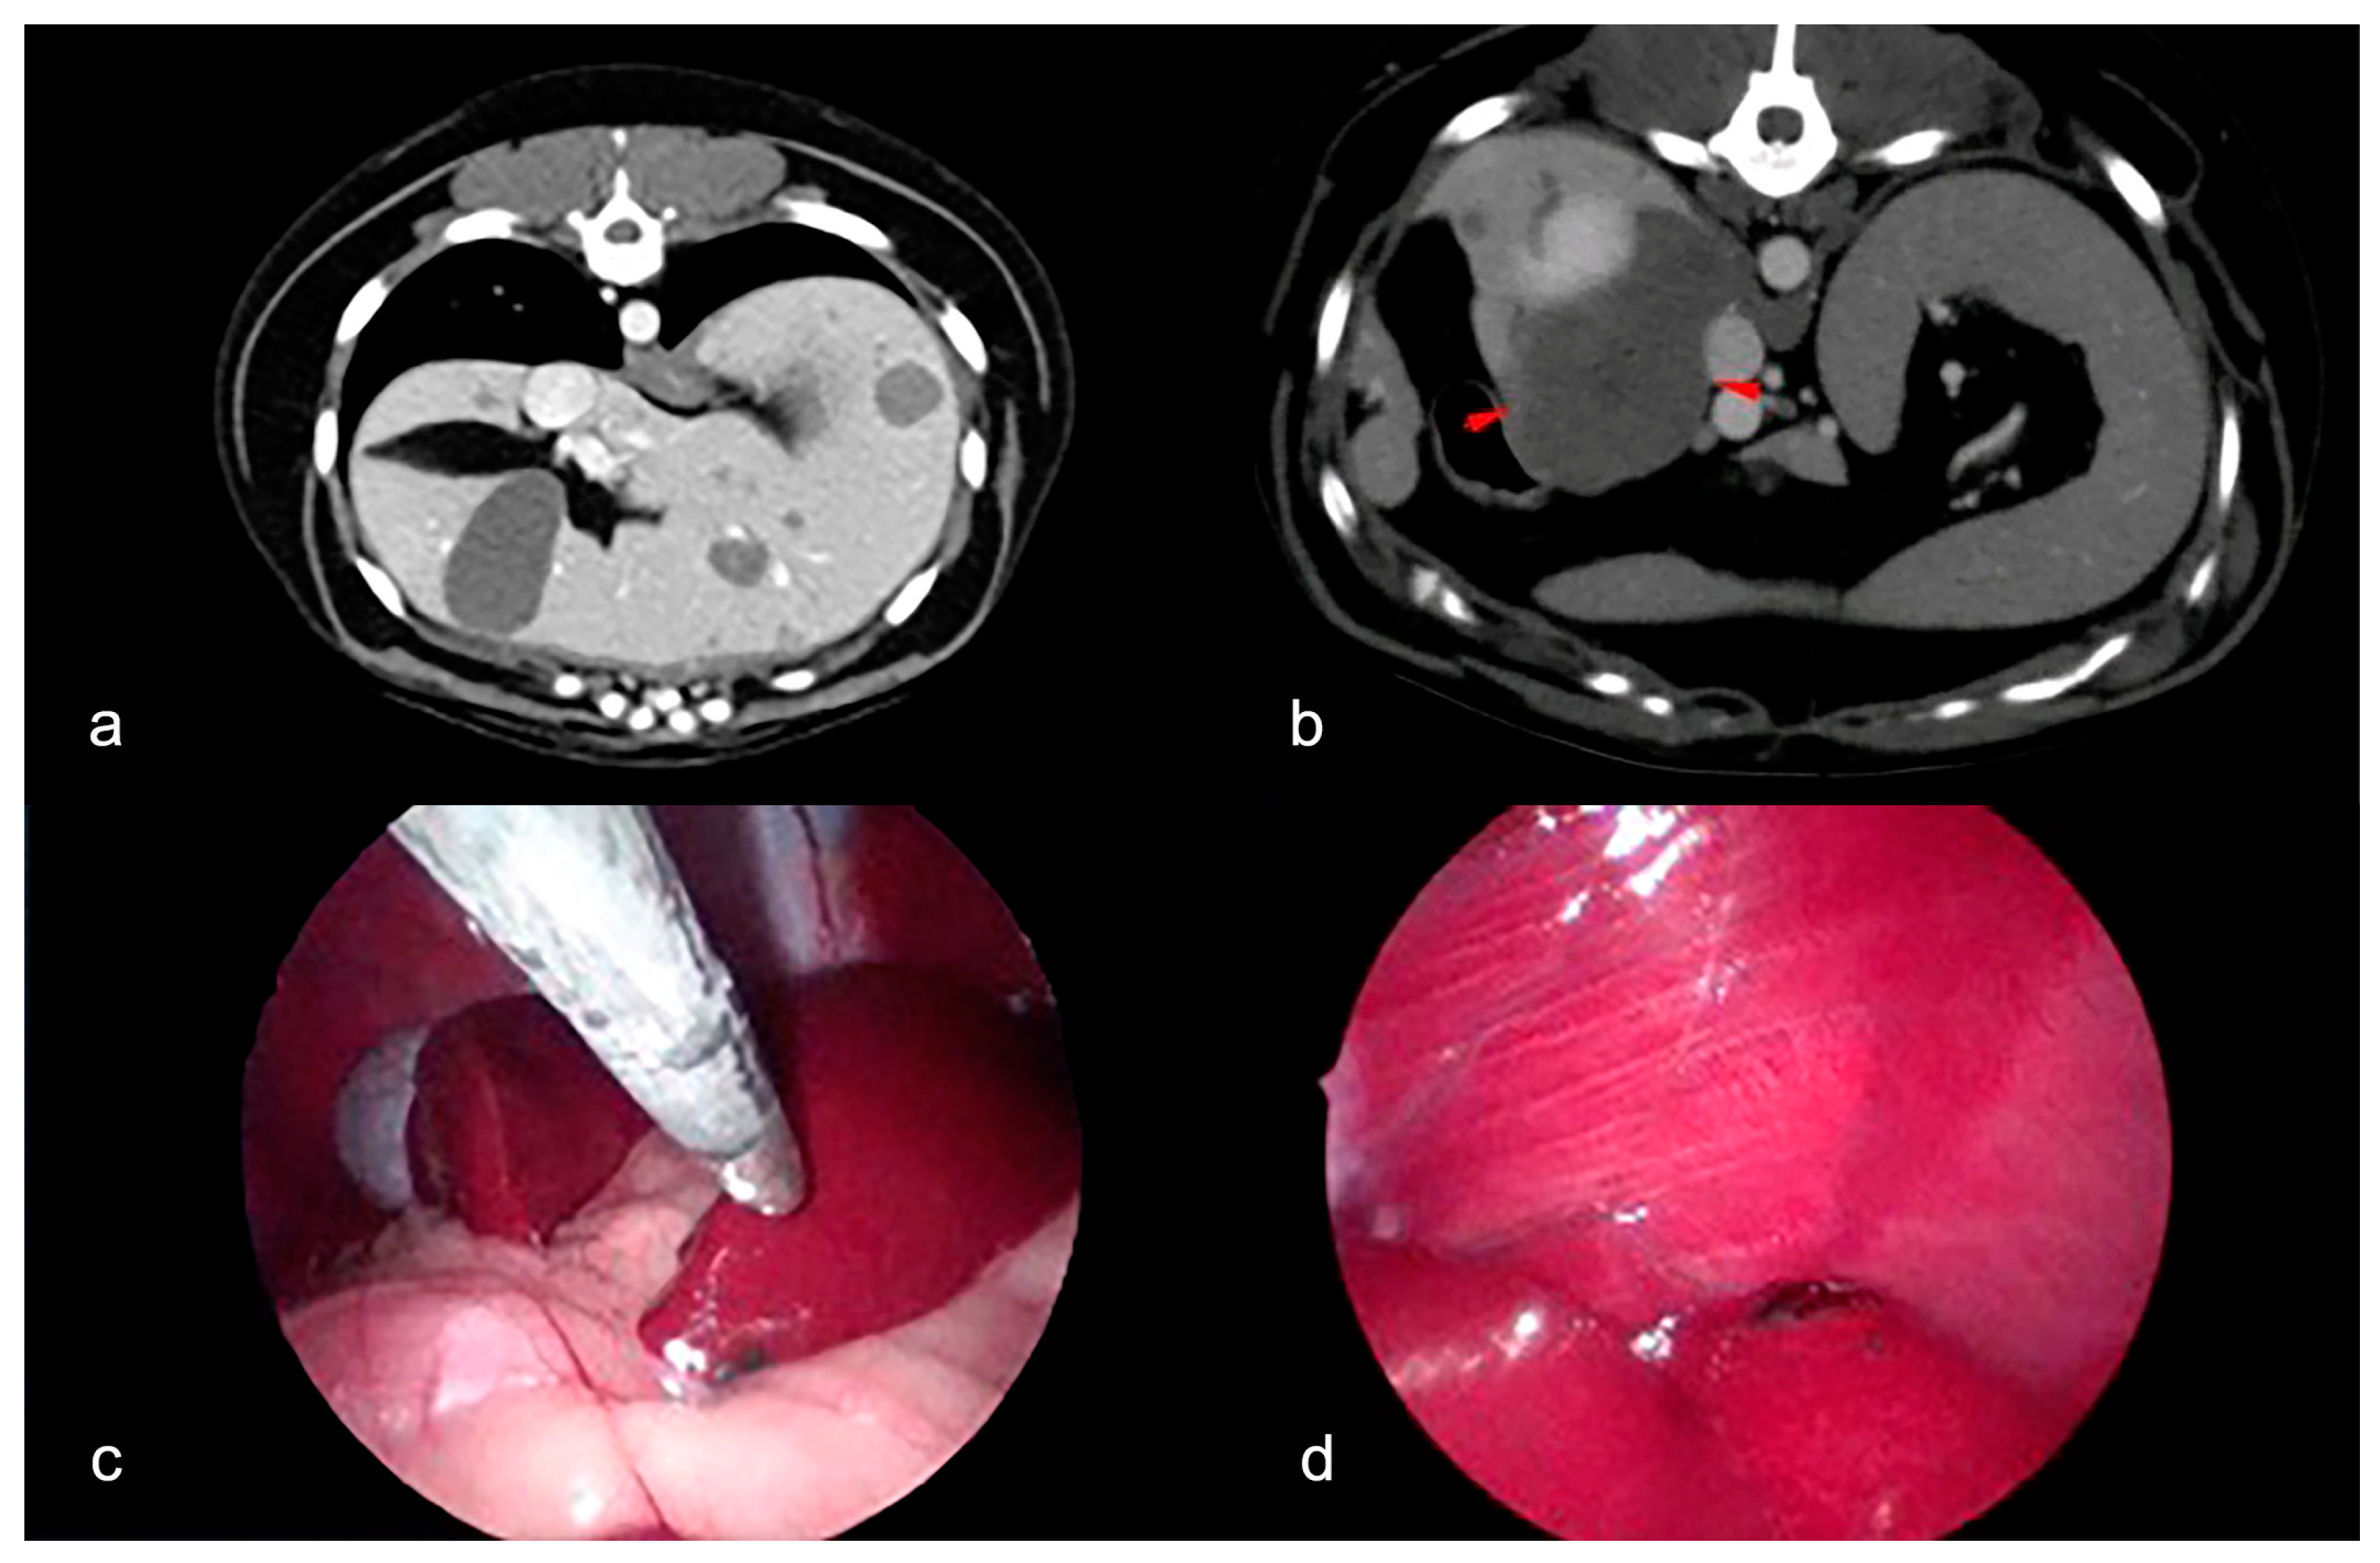

3.1. Clinical Findings